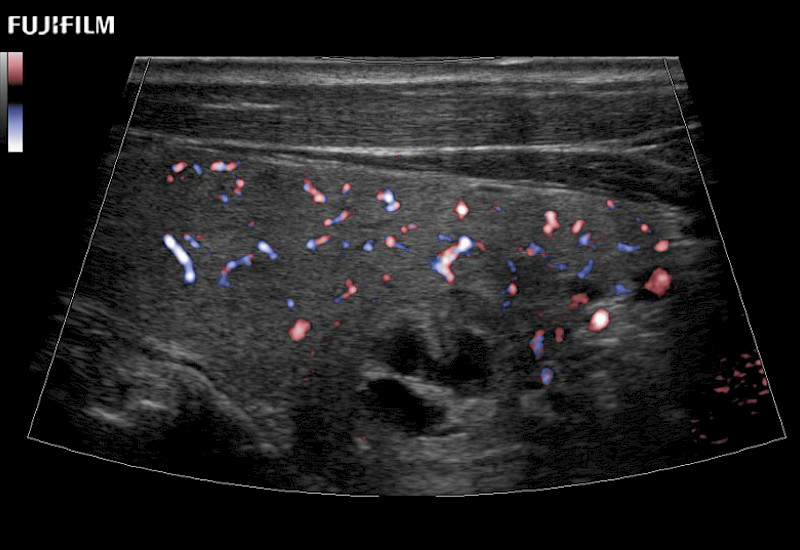

For precise surgical oncology ultrasound imaging, Fujifilm Healthcare offers premium level solutions that include:

Extraordinary high-resolution digital imaging

Multi-Parametric imaging modalities

Our dedication to Surgical Oncology allows us to offer superior image quality, outstanding system reliability and intuitive use of cutting edge technology.